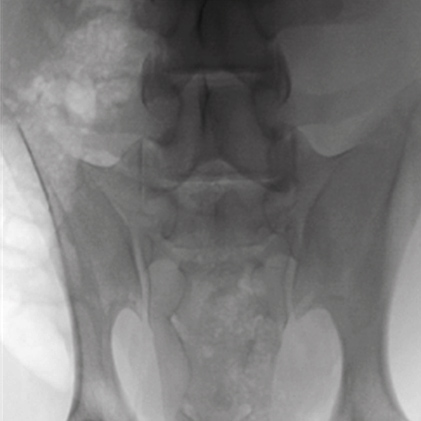

DSA(Digital Subtraction Angiography) helps various clinical diagnosis and procedures through the vessel image information after injecting contrast medium.